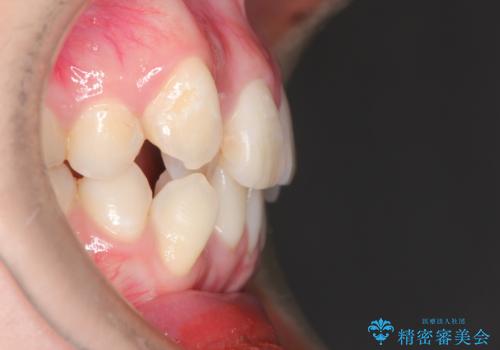

八重歯のワイヤーによる抜歯矯正 矯正治療と並行してセラミック治療も

- 八重歯と前歯のガタガタを主訴に来院されました。

左下の奥歯がすでに1本抜歯されており、ブリッジを装着されていました。

ブリッジを除去して、左下以外の上顎両側と右下の歯を合計3本抜歯して矯正する計画としました。